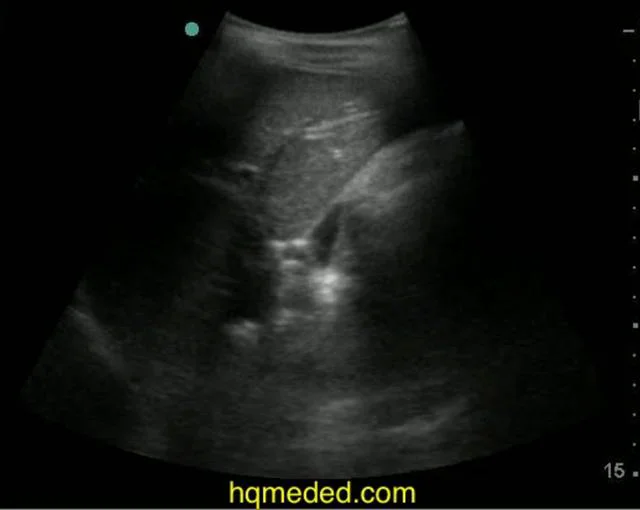

From vimeopro.com

Ultrasonography free fluid in pelvis on Vimeo Treatment For Free Fluid In Pelvis Treatment for free fluid in the pelvis depends on the cause. Identifying the symptoms associated with free fluid in the cul de sac is essential for early diagnosis and treatment. This is often a normal finding in women related to ovulation. The treatment for free fluid in the pelvis depends on the underlying cause. Small amount of free fluid in. Treatment For Free Fluid In Pelvis.